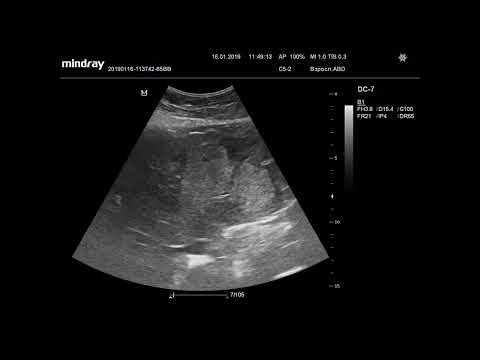

Ультразвуковая диагностика. Доктор Иогансен. Видеопримеры. Выпуск 111. Опухоль печени (5).

Представлены новые видеопримеры опухоли печени, выявленной при УЗИ. Ссылка на Дзен: Ссылка на RuTube: Ссылка на ВК видео: Ссылка на YouTube: / @dr.johansen